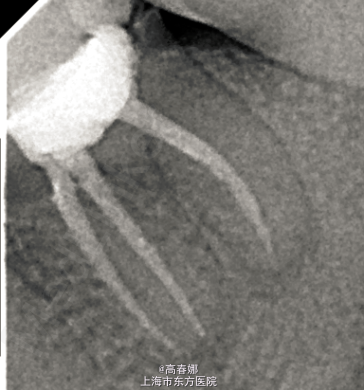

诊断:36慢性根尖周炎 处理: 一诊:36去除牙合面积髓腔内原充填物,探及近中颊舌根及远中根三根管,拔除坏死牙髓,近中两根管细小,10#及15#根管扩大锉疏通根管,双氧水及生理盐水交替冲洗根管,干燥,髓腔内置FC棉球,暂封,告常规医嘱,肿痛随诊。 二诊:一周后复诊,无不适主诉。查36扣诊(-),牙龈无红肿,FC棉球无臭味,无明显渗出。36去除暂封及FC棉球,手用PROTAPER SX锉预备根管中上1/3,根管长度测量,WAVE-ONE完成根管预备,预备过程中双氧水及生理盐水交替冲洗根管,干燥,髓腔内置FC棉球,暂封,告常规医嘱,肿痛随诊。 三诊:一周后复诊,无不适主诉。查36扣诊(-),牙龈无红肿,FC棉球无臭味,无明显渗出。36去除暂封及FC棉球,根充糊剂+大锥度牙胶尖侧压充填,X线示适充,锌基,树脂充填,调合,抛光,告常规医嘱。建议观察一至二周全冠修复。

随访:两周后复诊,患牙叩诊无不适,牙龈无红肿。 讨论:干髓术治疗失败,常发生根尖周炎。同时干髓术,随着时间的推移会导致根管钙化,造成根管细小,严重者导致根管闭锁,给根管治疗带来一定的难度。